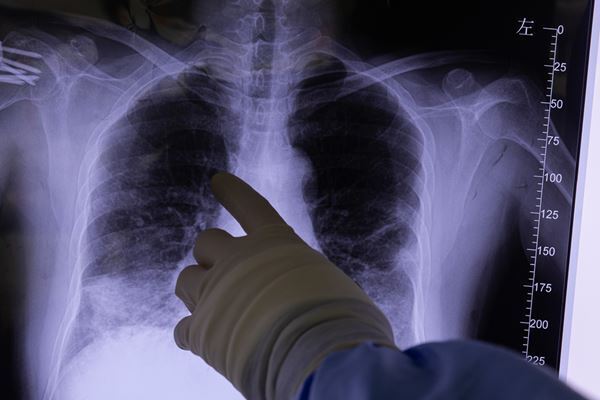

(写真:時事通信)